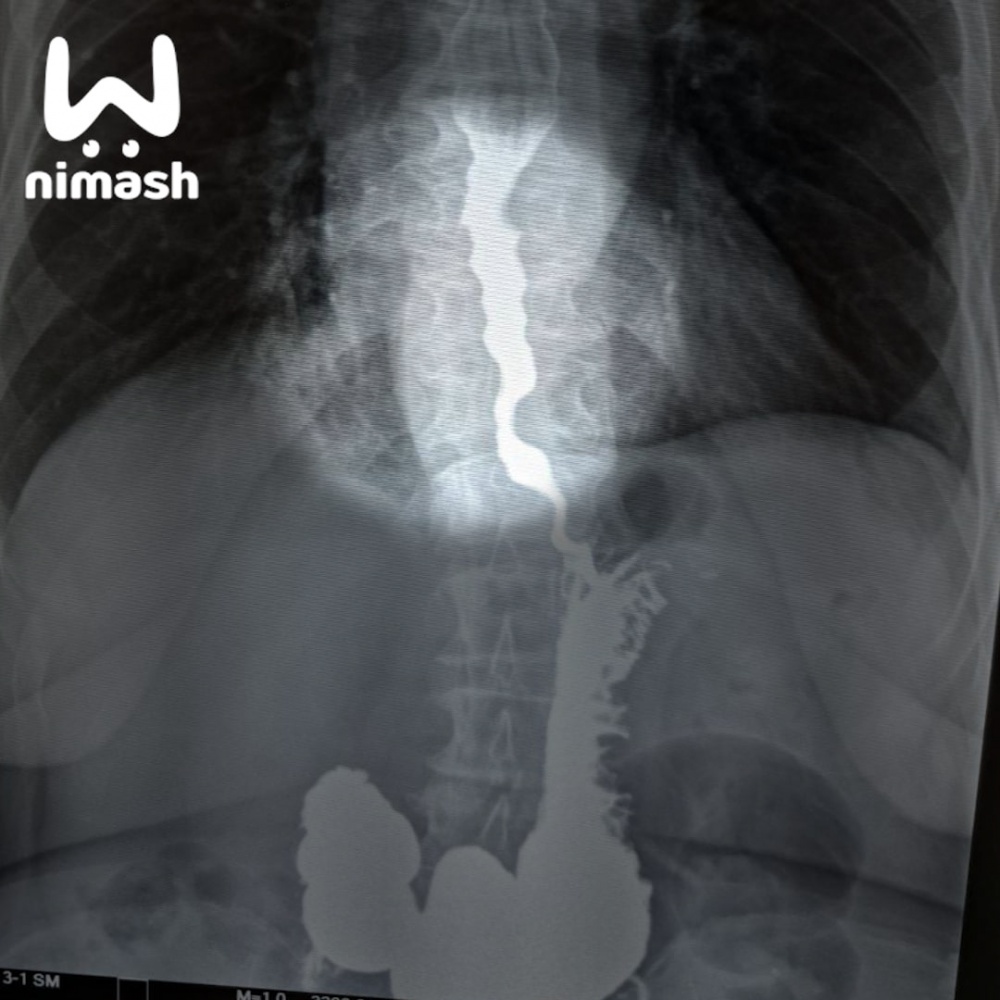

Пожилую пациентку, которая не могла есть и даже пить из-за редкой болезни, спасли хирурги ЦГБ Арзамаса. Они провели уникальную операцию по расширению пищевода.

У 70-летней пенсионерки нашли ахалазию — патологию, при которой орган сужается до аномальных размеров и не пропускает ни пищу, ни жидкость. Состояние стремительно ухудшалось, и врачи решились на операцию — первую такого рода в области. В пищевод ввели специальную пластиковую трубочку и плавно надули.